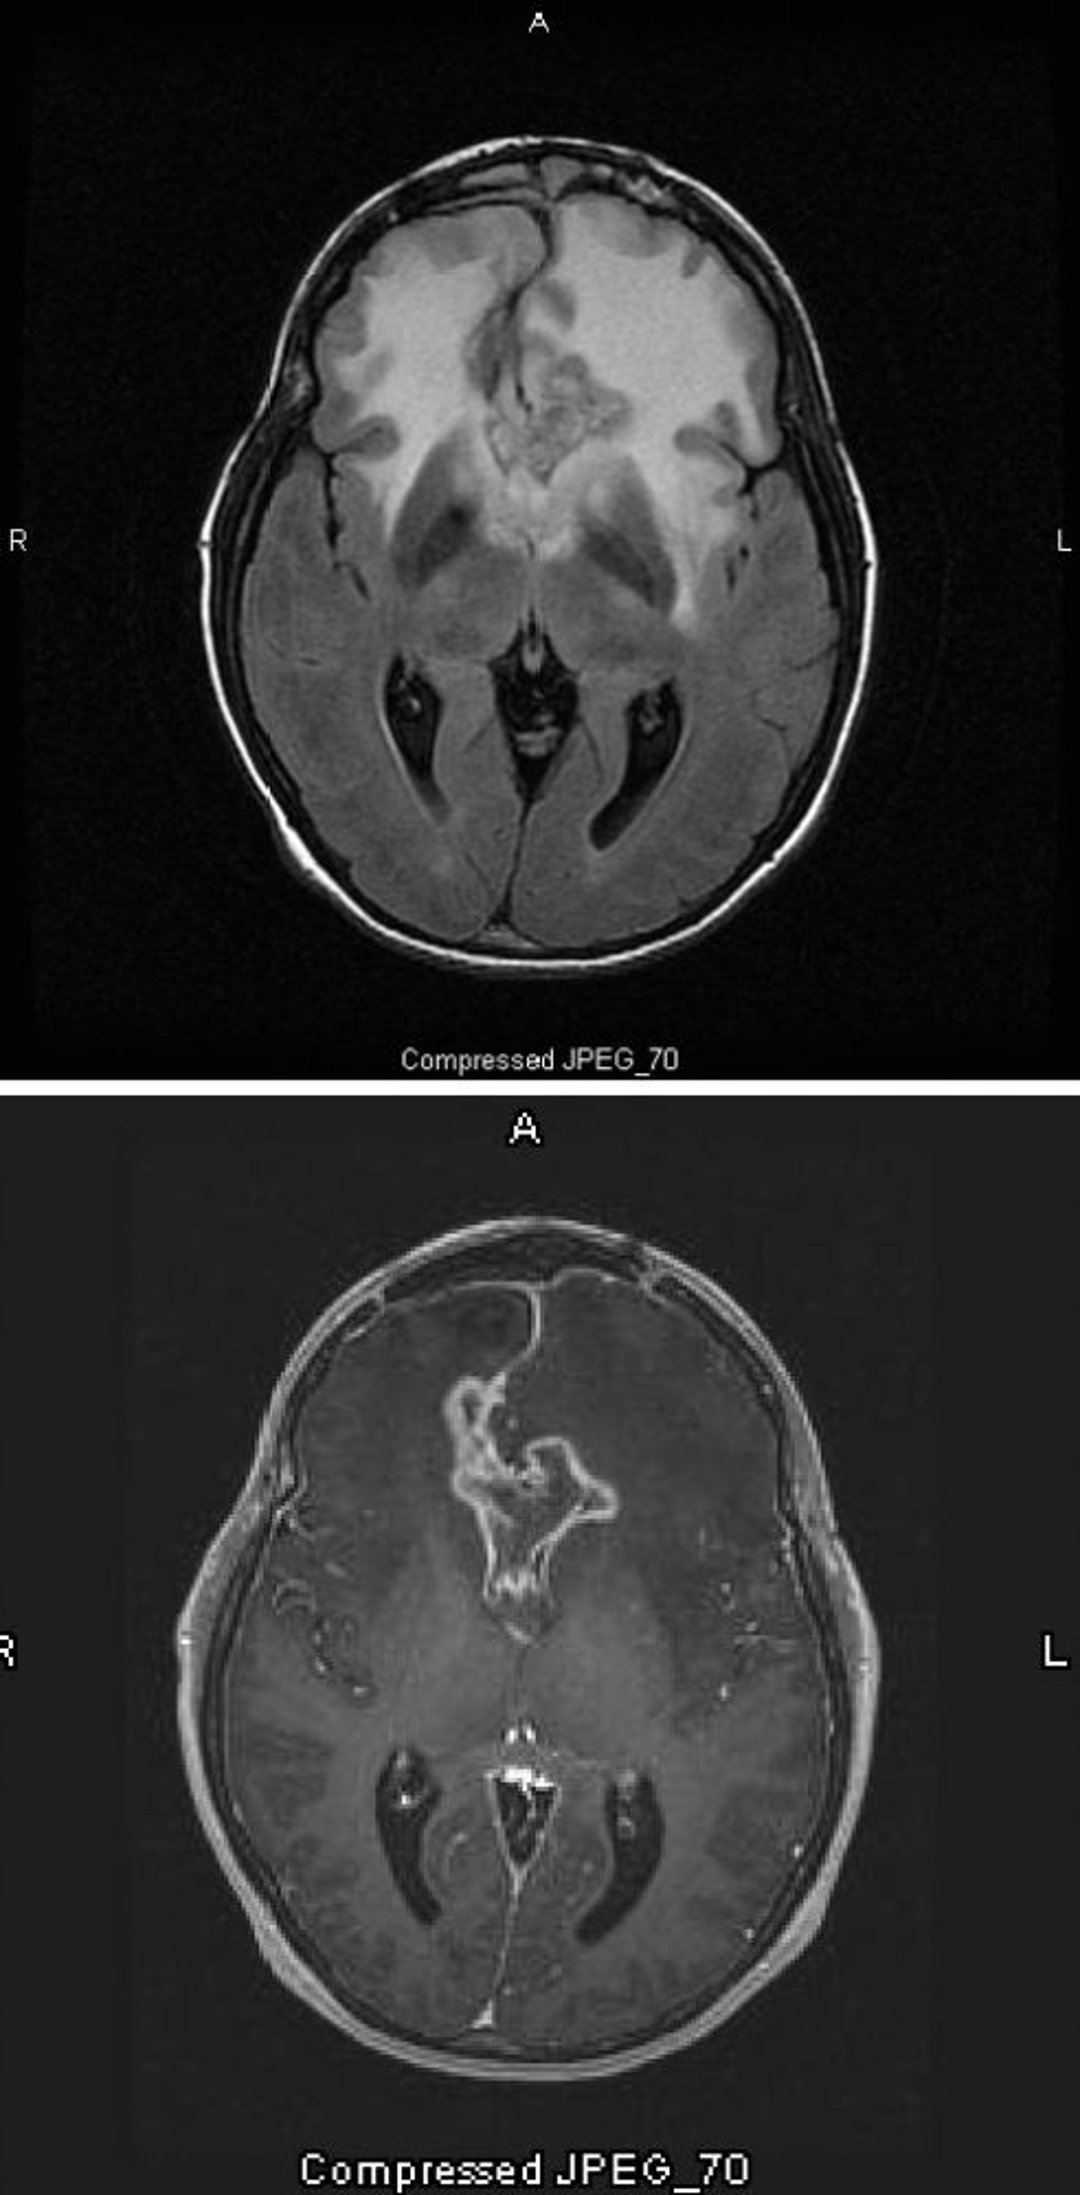

Glioblastome

L'IRM T2-FLAIR (en haut) montre un grand signal bilatéral blanc (hyperdensité) autour d'un glioblastome, qui est l'astrocytome de grade le plus élevé et le plus malin. Ce glioblastome particulier est appelé gliome papillon parce que le signal blanc autour de la tumeur a une forme en ailes du papillon; il est provoqué par un œdème cérébral. Sur l'IRM pondérée en T1 (en bas), le contraste délimite le bord de la tumeur (prise de contraste en anneau). L'œdème apparaît comme une zone sombre (hypointensité) en T1.

Images courtesy of William R. Shapiro, MD.